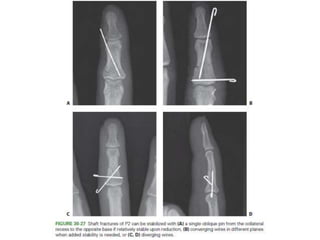

Middle Phalanx Fracture- Treatment Options

• Condylar fractures

– CRIF- converging or diverging.